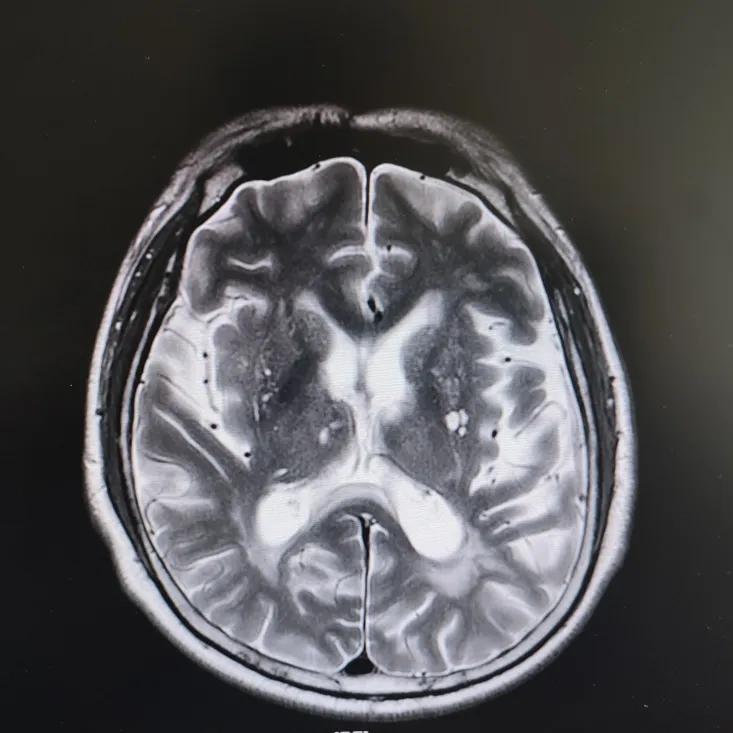

患者头部磁共振影像

凭着多年诊治疑难杂症的丰富经验,赵主任敏锐地意识到这“痴呆”可能是假象,背后另有隐情。他果断建议进一步做特殊感染筛查。果然,检查证实这位患者同样是感染了苍白密螺旋体!经过精准的抗感染治疗,奇迹发生了:患者的反应变快了,眼神灵活了,走路也恢复了正常步态。最终的诊断是“麻痹性痴呆”——一种由神经梅毒引起的、可治疗逆转的“痴呆”类型!